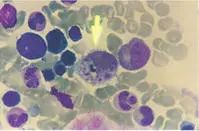

流行性出血熱,國際又稱腎綜合癥出血熱,是一種經(jīng)鼠傳播、由漢坦病毒引起的,臨床上以發(fā)熱、出血和腎損害為主要特征的嚴(yán)重的急性傳染病。在我國屬于乙類傳染病。

人感染漢坦病毒后潛伏期通常為7-14天,也偶見短至4天或長至2個(gè)月者。典型臨床表現(xiàn)具有三大主征,即發(fā)熱、出血和腎損害。

可出現(xiàn)眼瞼浮腫、結(jié)膜充血,水腫,有點(diǎn)狀或片狀出血;

上腭粘膜呈網(wǎng)狀充血,點(diǎn)狀出血和腋下皮膚有線狀或簇狀排列的出血點(diǎn)。患者束臂試驗(yàn)陽性。